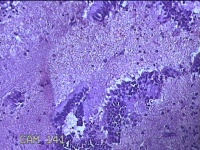

性别

女

年龄

44岁

临床诊断

子宫异常出血;子宫肌瘤;子宫内膜息肉

一般病史

阴道流血1月。

标本名称

宫颈管内膜

大体所见

纱布一块,内有灰白暗红色不规则碎组织1.5x1x0.2cm一堆。

图2